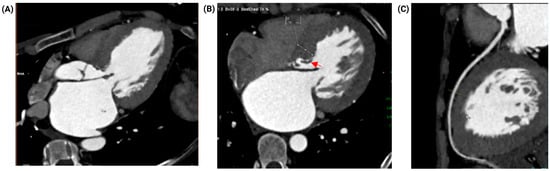

Combined Fixed and Dynamic Left Ventricular Outflow Tract Obstruction in Hypertrophic Cardiomyopathy Due to a Coexisting Subaortic Membrane: A Case Report

Introduction: Hypertrophic cardiomyopathy (HCM) is a common myocardial disease worldwide and is associated with heart failure symptoms and sudden cardiac death. In a subset of patients, it may produce dynamic left ventricular outflow tract obstruction (LVOTO) and systolic anterior motion (SAM)-related mitral valve dysfunction through drag forces and altered mitral–septal geometry. In contrast, subaortic stenosis caused by a subaortic membrane is an uncommon congenital lesion that may lead to fixed subvalvular LVOTO in adulthood. The coexistence of these entities is rare and can substantially complicate diagnosis and management. Case presentation: A 51-year-old woman with HCM, paroxysmal atrial fibrillation, and heart failure presented with acute decompensation and cardiogenic shock. After initial hemodynamic stabilization and cardioversion for atrial fibrillation with rapid ventricular response, multimodality imaging with transthoracic and transesophageal echocardiography, coronary computed tomography angiography, and cardiac magnetic resonance demonstrated dual LVOTO, with a dynamic component related to HCM/SAM physiology and a fixed component caused by an elongated subaortic membrane, accompanied by severe SAM-related mitral regurgitation. Echocardiography showed a resting peak LVOT gradient of 49 mmHg, increasing to 85 mmHg with the Valsalva maneuver. After exclusion of obstructive coronary artery disease and evaluation for selected phenocopies, the patient underwent septal myectomy, subaortic membrane resection, and adjunctive mitral valve plication. Early postoperative echocardiography showed reduction in the maximum provoked LVOT gradient to 38 mmHg and improvement of mitral regurgitation from severe to mild. At 3-month follow-up, she remained in sinus rhythm, improved to New York Heart Association functional class II, and had no documented readmissions for heart failure. Conclusions: Combined fixed and dynamic LVOTO due to concomitant subaortic membrane and HCM is exceedingly rare. Accurate diagnosis requires a high index of suspicion and a multimodality imaging strategy to define the obstructive mechanisms and support mechanism-based surgical management and avoid incomplete treatment when a coexisting fixed lesion is present. Full article

Figure 1